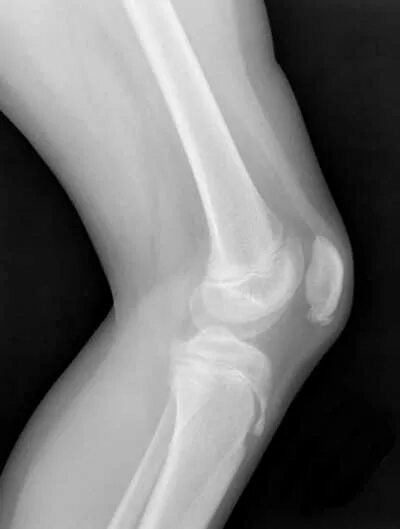

Болезнь осгут шляттера